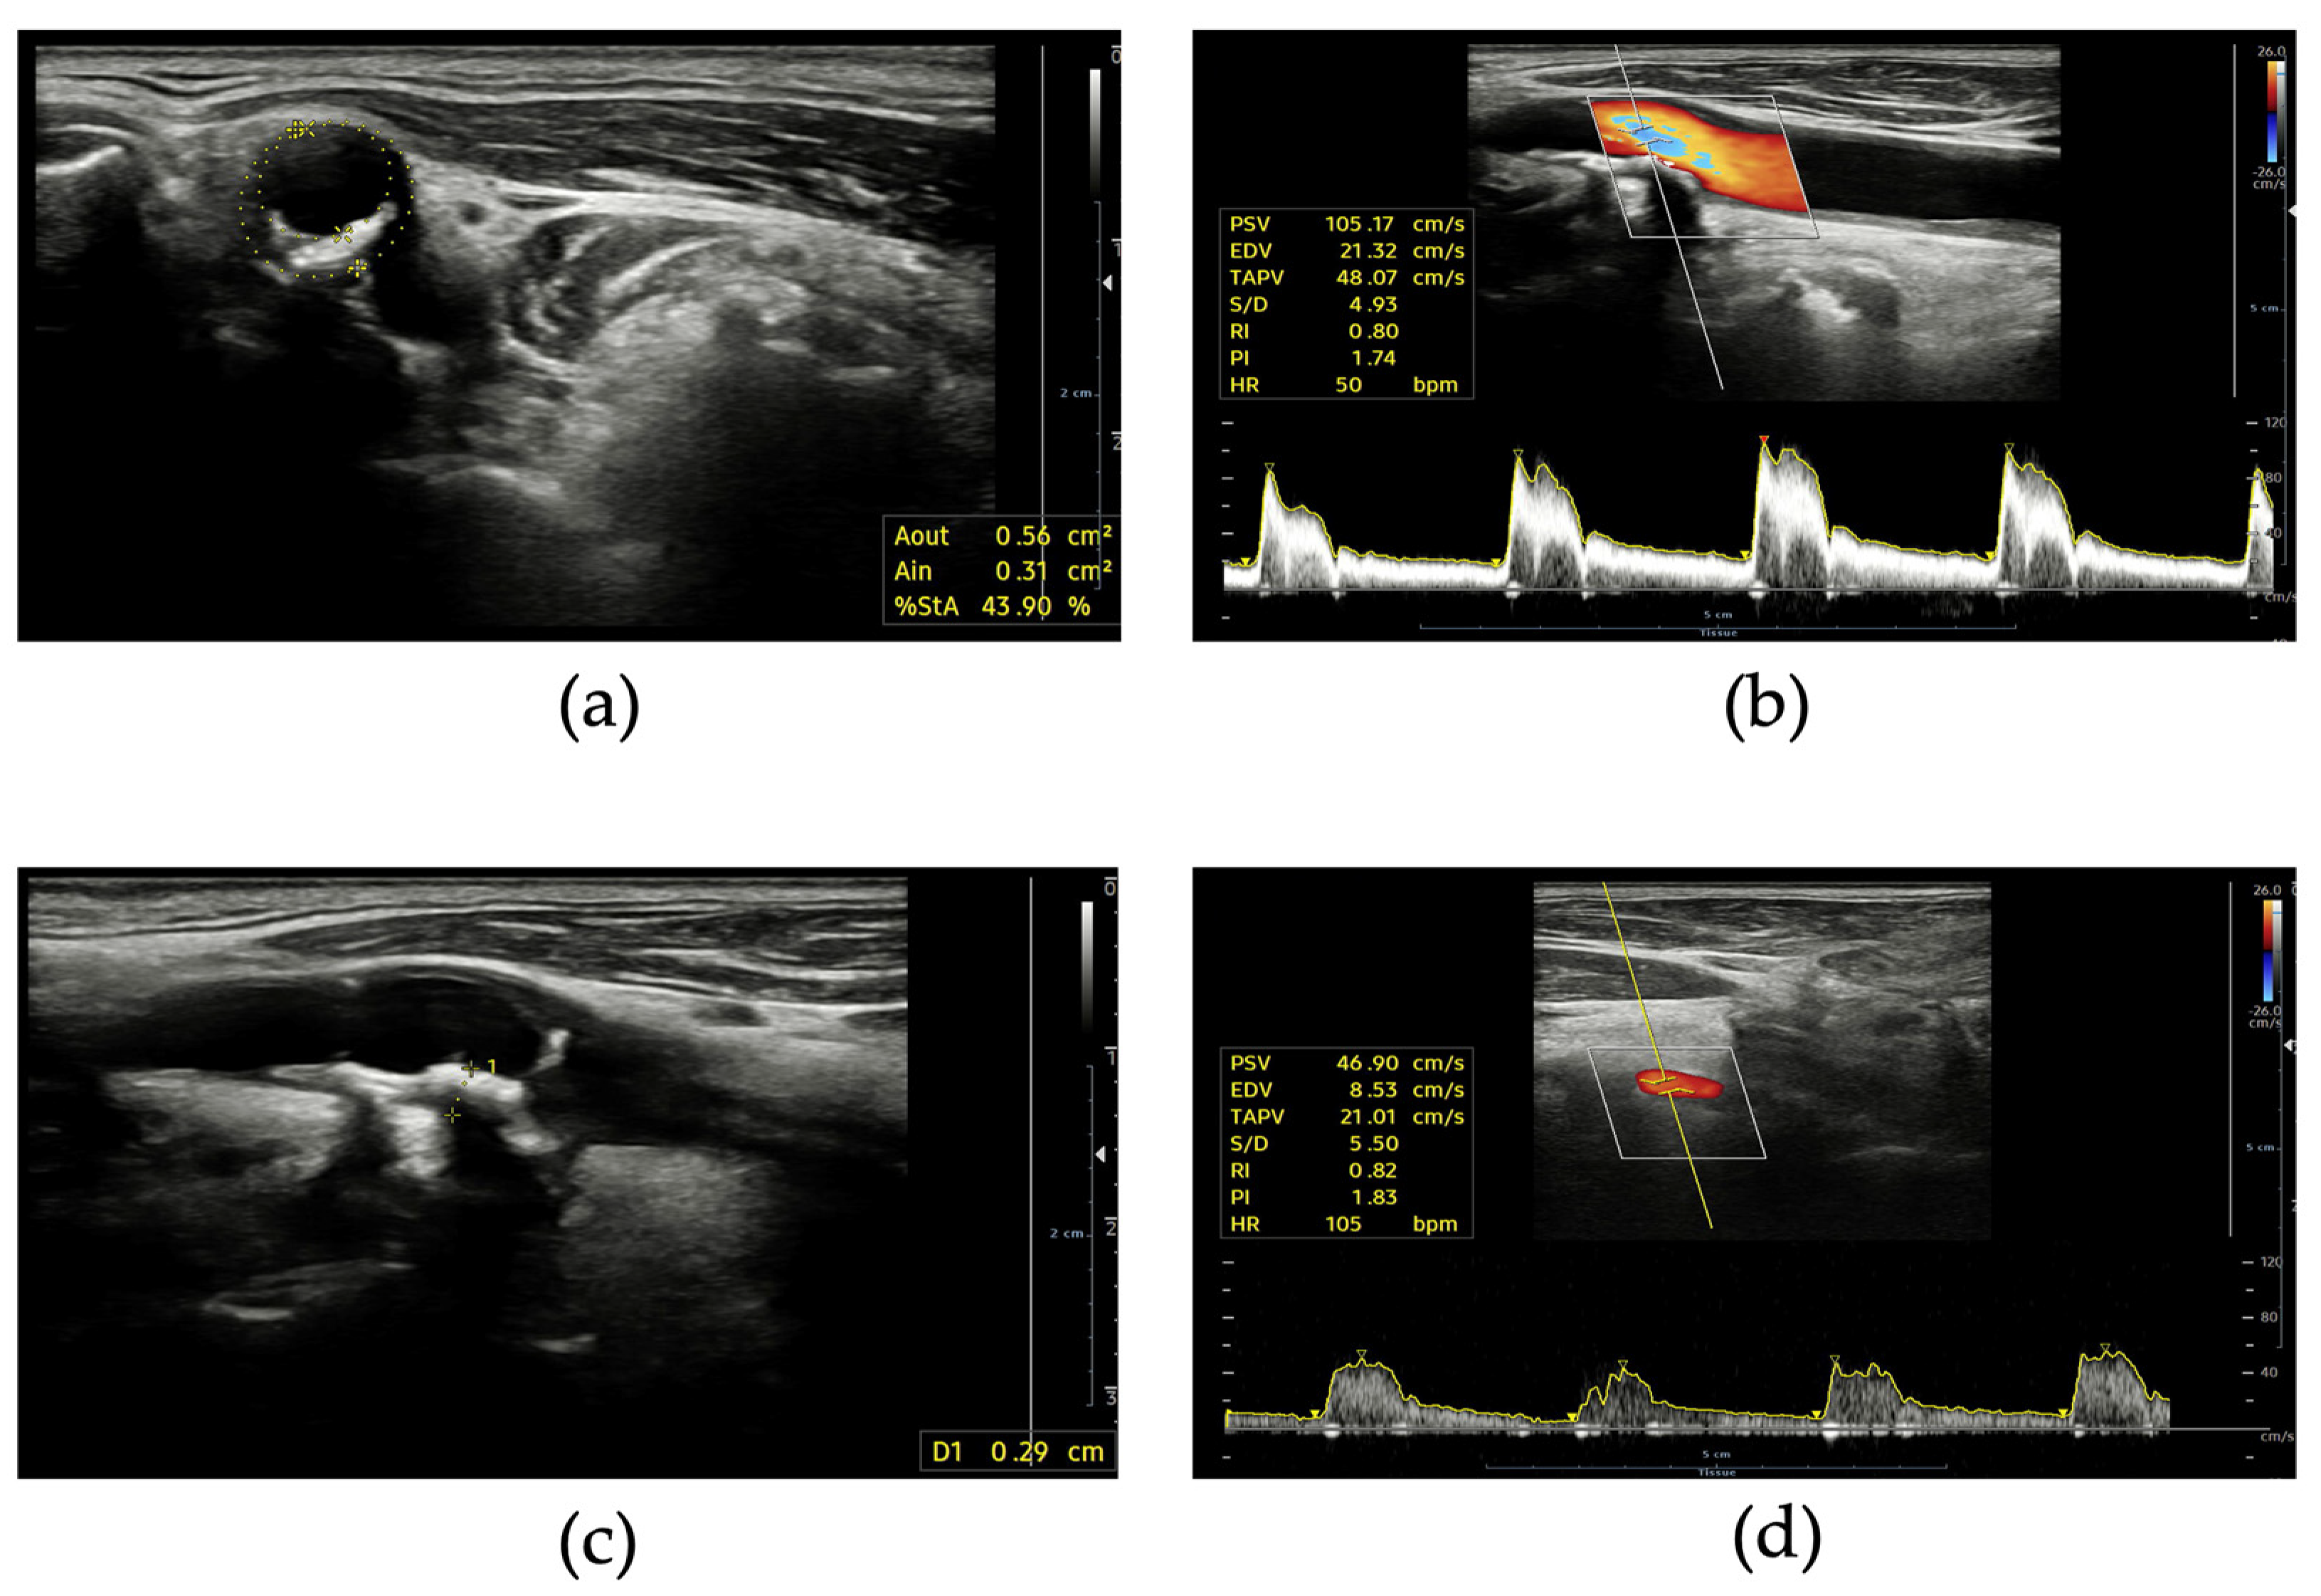

11. Cardiac Magnetic Resonance Imaging in Cardiovascular Prevention